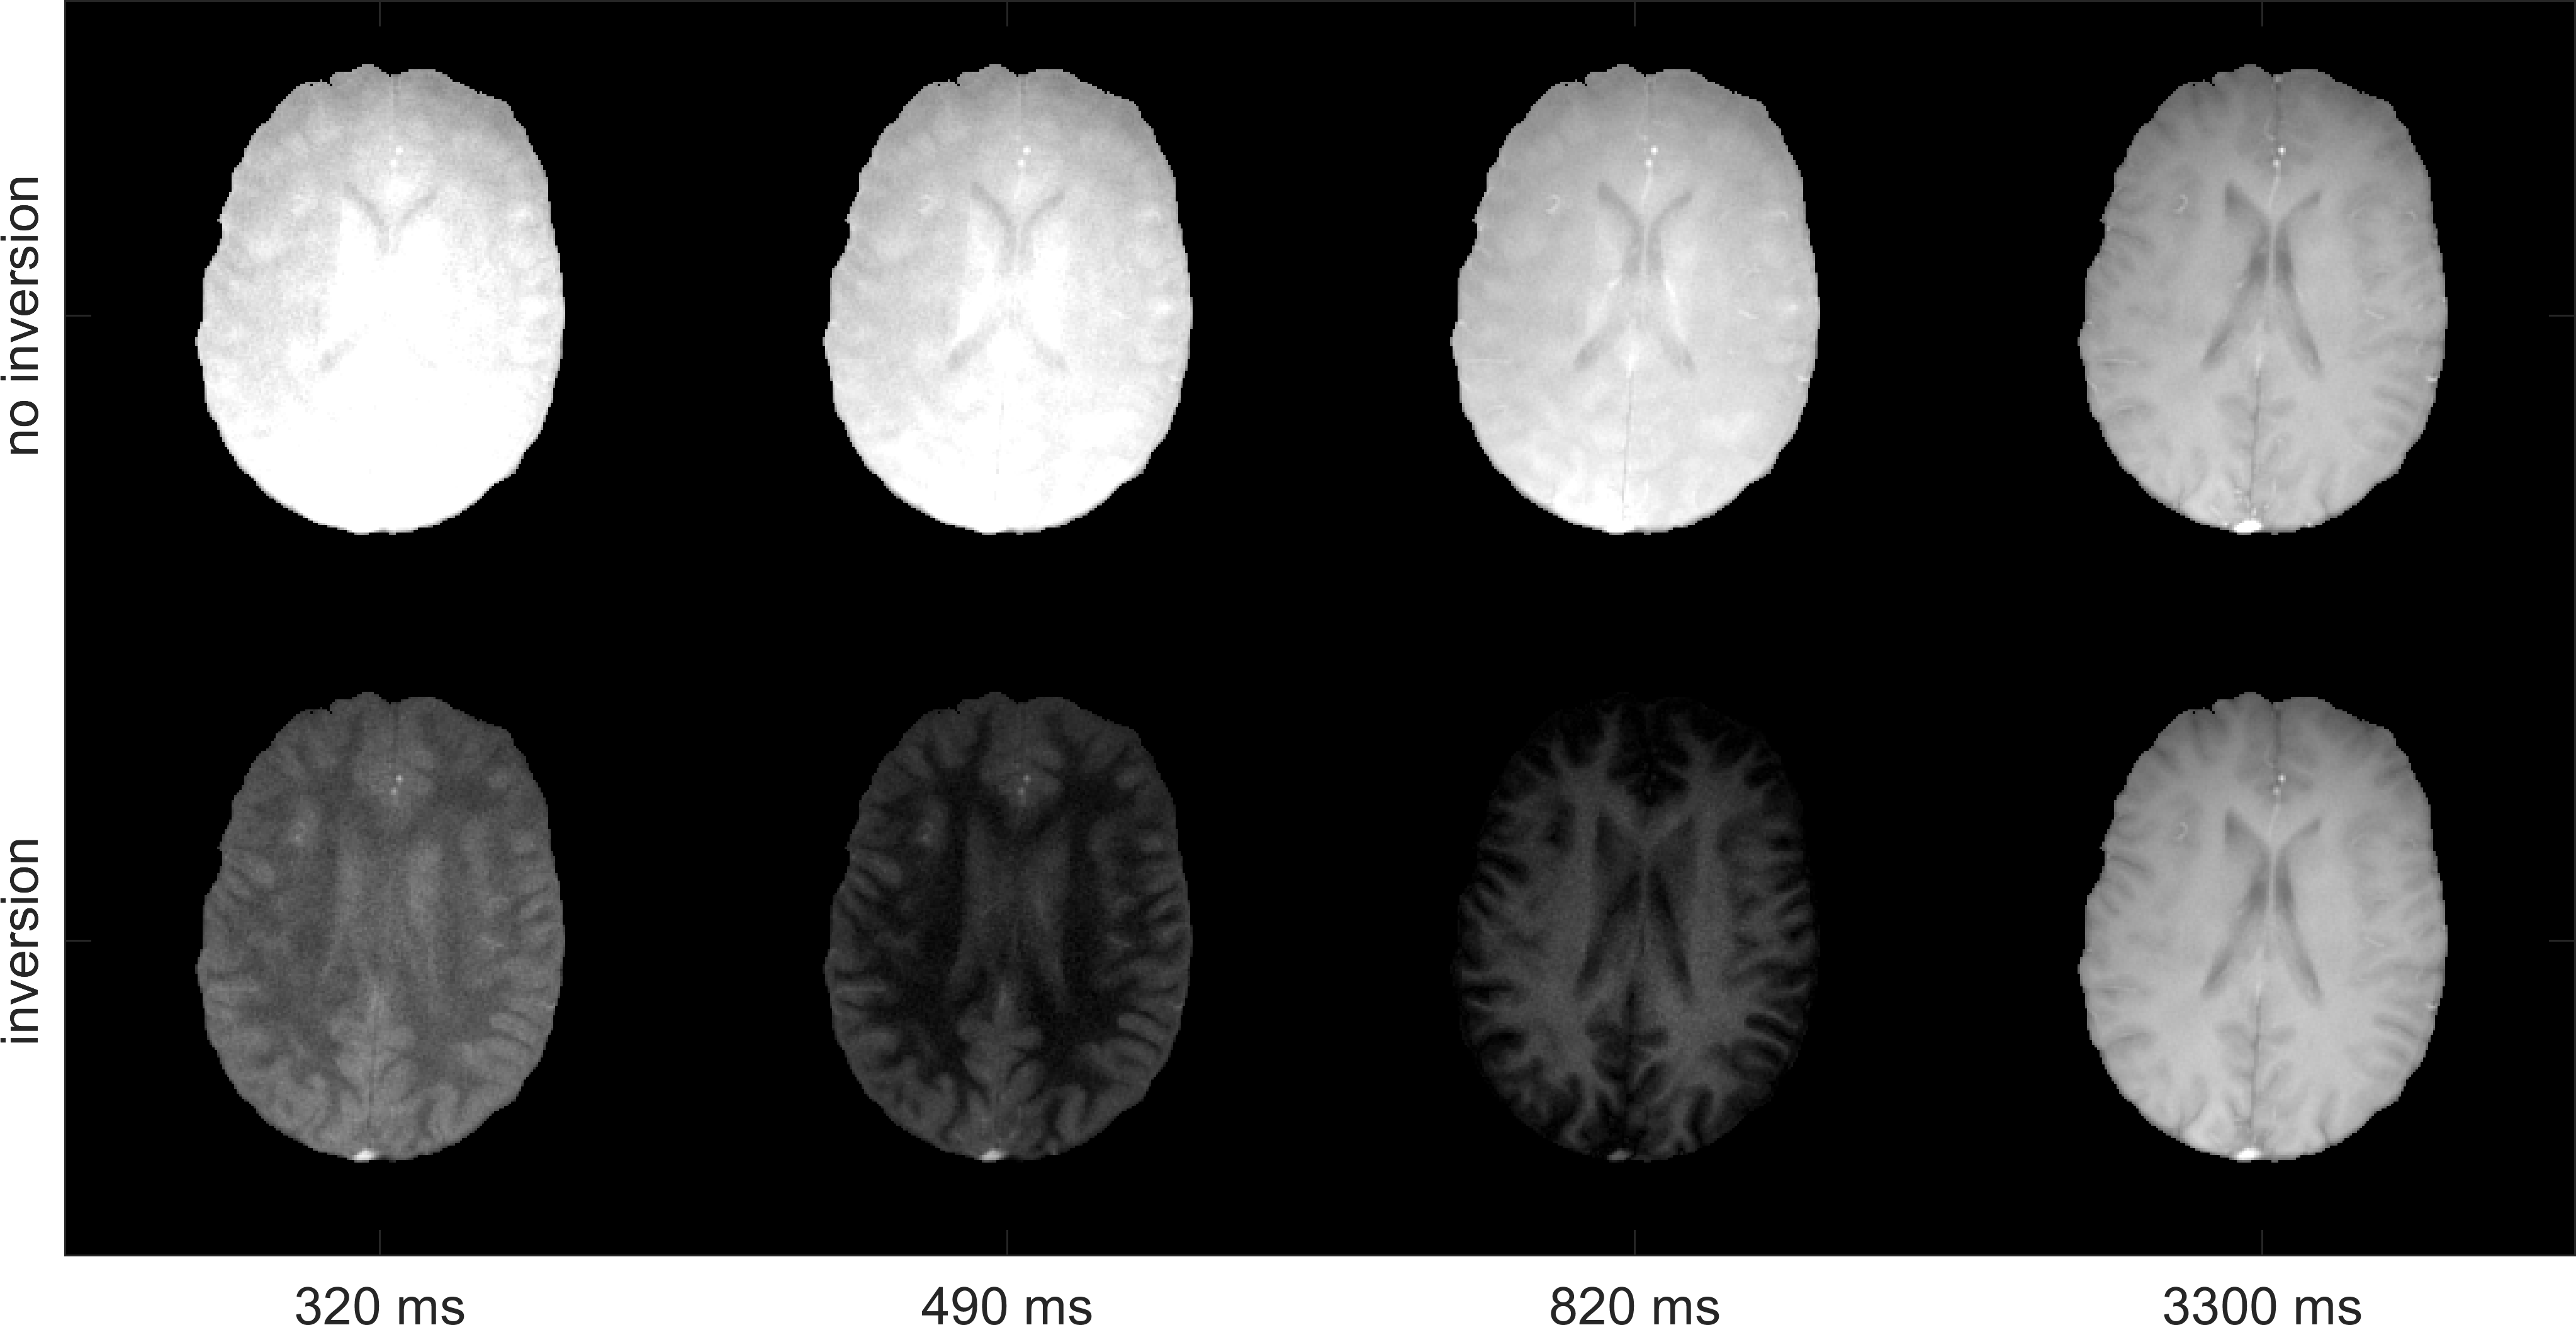

Figure 2 shows exemplary time points of both measurements. The inversion-prepared acquisition features the successive zeroing of different tissues.

Figure 2: Exemplary time points from sliding window reconstruction of measurement without inversion (top) and measurement with inversion preparation (bottom). The inversion-prepared acquisition features the successive zeroing of different tissues.